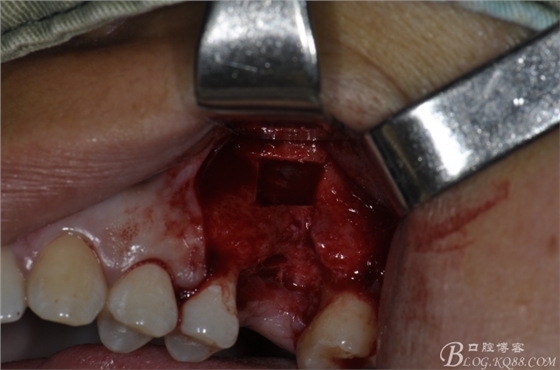

術(shù)中照片。

超聲骨刀切開(kāi)骨外板